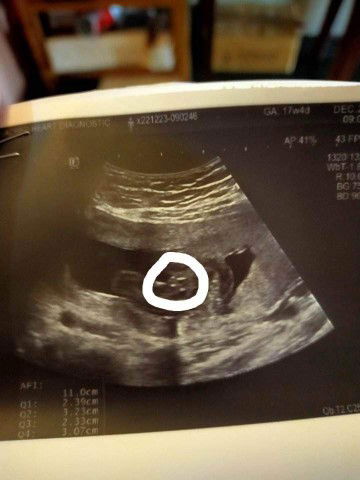

It's a boy ❤️

Lahat na ba Team May baby boy? Here's my baby's gender reveal. Pasikat sa kanyang pekoy.

team May din, baby boy, nung inuultrasound palang ako nakita ko na yan sa monitor sabi ko maam pututoy po ba yan? tawa yung naguultrasound sakin lalaki nga talaga 🤣💖